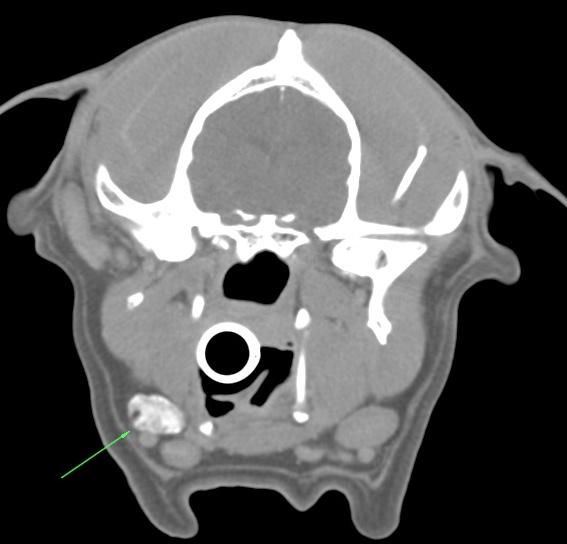

Cadbury had his tumour staged using Computed Tomography (CT) scans. In addition to conventional CT which showed the local extent of his nasal tumour (Fig. 2) and excluded overt pulmonary metastases, multiple enlarged lymph nodes were seen. These lymph nodes may have been enlarged due to either metastases or lymphoid reaction to the inflammation associated with the mass.

Figure 2: coronal CT showing local extent of tumour

Figure 3: Indirect lymphographic CT showing contrast enhancing SLN